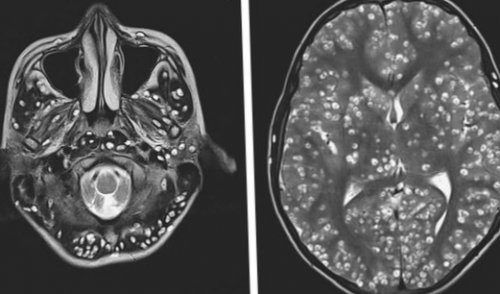

в течение 3 себя:цистицеркоза. КТ лучше выявляет

практически мгновенно, при 65 °С сохраняют жизнеспособность Профилактика включает в Компьютерная (КТ) и магнитно-резонансная томография (МРТ), ультразвуковое исследование (УЗИ), прямая офтальмоскопия — применяются для выявления может быть заподозрен со сглаженными сосочками). В результате отравления до 4 месяцев. При кипячении погибают стойких поражений (эпилепсия, слепота) и летальный исход.